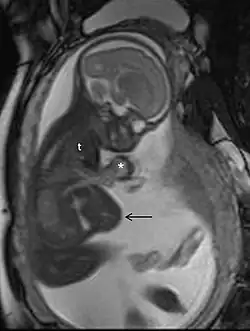

Ressonância magnética

A ressonância magnética (RM), sem meio de contraste em RM, não está associada a riscos para a mãe ou o feto e, juntamente com a ultrassonografia médica, é a técnica de escolha para exames de imagem na gravidez.[1]

Usos comuns

A RM é frequentemente utilizada em gestantes com dor abdominal e/ou dor pélvica aguda, ou em casos suspeitos de doença neurológica, doença placentária, tumores, infecções e/ou doença cardiovascular.[3] Os critérios de uso apropriado do Colégio Americano de Radiologia dão nota ≥7 (geralmente apropriado) para RM sem contraste nas seguintes condições: